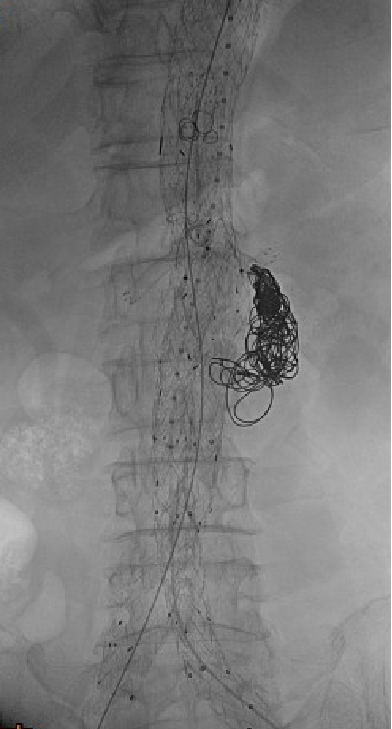

治疗方案:PMEG拓展近端锚定区,重建CA、SMA、RRA和LRA

35-14-140mm分叉型支架,缝制内分支并固定,RRA、LRA:5mm Viabahn,CA、SMA:7mm Viabahn

分支预置导丝,回装支架

超选SMA,桥接8-100mm Viabahn,内衬8-60mm Absolute裸支架

超选CA,桥接8-100mm Viabahn

超选RRA烟囱支架,桥接6-100mm+6-50mm Viabahn

超选LRA烟囱支架,桥接6-100mm Viabahn

右侧:16-16-140mm Excluder髂腿;

左侧:16-16-120mm Excluder髂腿

术后造影